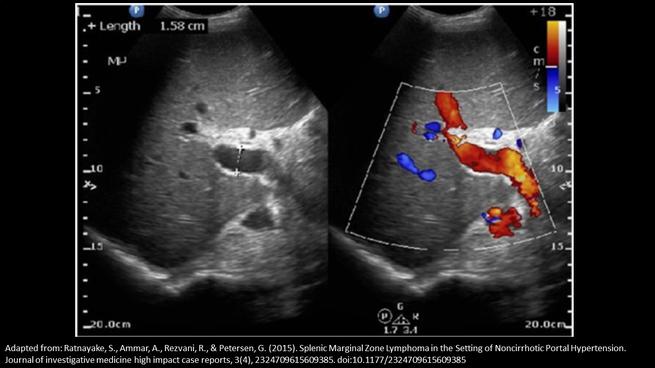

Which of the following statements correctly, describes the findings on the image?

The portal vein is measured correctly and demonstrates possible portal hypertension